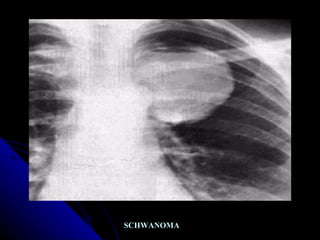

SCHWANOMA